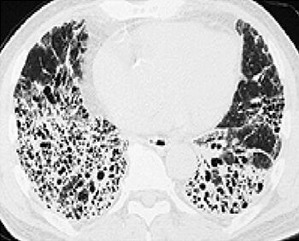

肺が繊維化してるから余命数年だろ

こんなだからな

肺真っ白になったというニュース流れてたし、後遺症が心配だな

60前で肺やられると社会生活かなり制限される